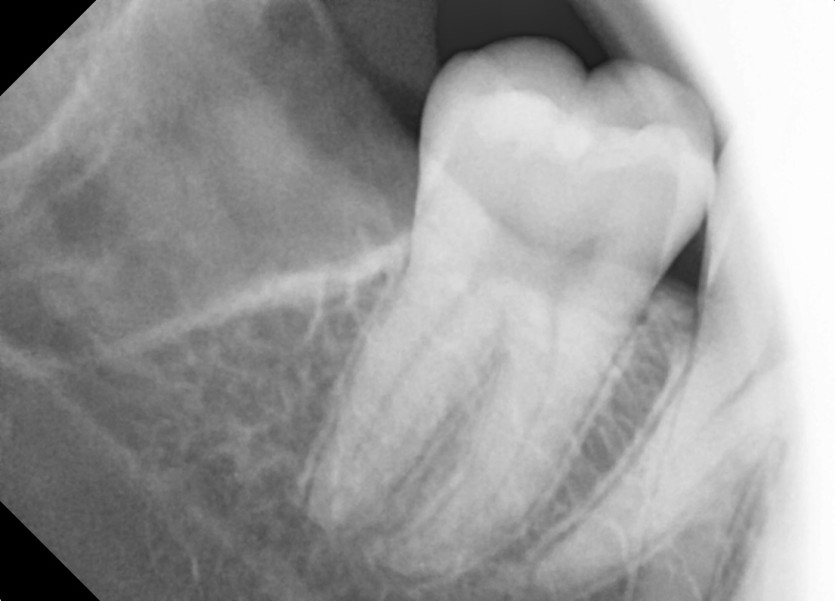

#28,38,48 사랑니 발치

구강 외과 전문의가 당일 발치했습니다.